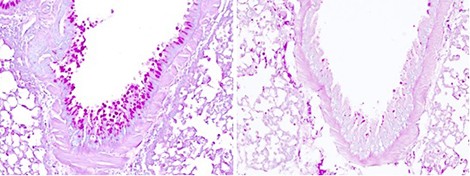

© Corinne Cayrol and Jean-Philippe Girard, IPBS, CNRS / Université Toulouse III—Paul Sabatier Mucus production in lung after inhaling allergen (lung sections; mucus shown in magenta). Excessive mucus production is characteristic of allergic asthma. The IL-33 protein, a major factor predisposing humans to asthma, detects allergen protease activity. Activated by proteases, IL-33 sets off a cascade of reactions, including mucus production, that are associated with asthma and other allergic diseases. When IL-33 activation is inhibited (see image on right), these reactions are not triggered.

A team of Inserm and CNRS researchers from the Institute of Pharmacology and Structural Biology—or IPBS (CNRS / Université Toulouse III—Paul Sabatier)—have identified a protein that acts like a sensor detecting various allergens in the respiratory tract responsible for asthma attacks. Their study, codirected by Corinne Cayrol and Jean-Philippe Girard, is published on 19 March 2018. These scientists' work offers hope for breakthroughs in the treatment of allergic diseases. What do mold, pollen, and cockroaches have in common? Though they correspond to three different kingdoms of life, they can all cause asthma attacks in people sensitive to them. And all of them, despite their very different compositions, contain enzymes called proteases . The IPBS team has identified a human protein that reacts to many environmental allergens: interleukin-33 (IL-33). When allergens enter the human respiratory tract, they release proteases that hack IL-33 molecules into extremely reactive pieces triggering the chain reactions behind allergy symptoms.